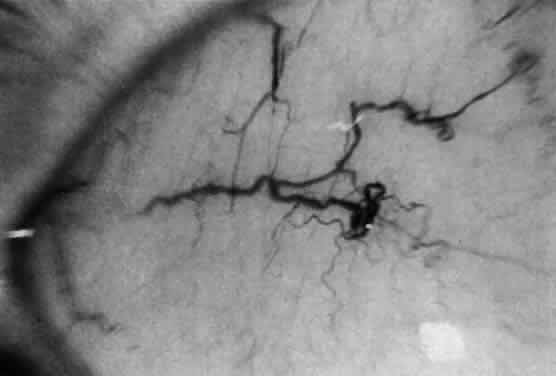

The pathologic hallmark of types A and B is the Niemann-Pick cell, which is a lipid-laden foam cell133 (Fig. 14). Sphingomyelin accumulates in the brain and autonomic ganglia. The neurons become swollen and have a pale cytoplasm. Ultrastructurally, the cells contain concentric lamellated bodies representing storage cytosomes. Inclusion profiles in the viscera, lymph nodes, and foam cells also correlate with an increase in sphingomyelin content. Diagnosis can be made readily by enzymatic determination of ASM activity in cells and tissues. More than 300 cases of type A and B NPD have been reported. Prenatal diagnosis has been accomplished by enzyme assays of cultured amniotic fluid cells in types A and B.

Fig. 14. Foam cells in bone marrow aspirate of patient with Niemann-Pick type B. Giemsa stain.